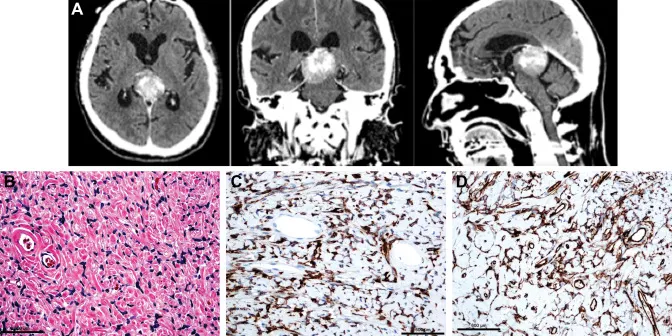

神经影像学综述《Neuroimaging in emergency: a review of possible role of pi...